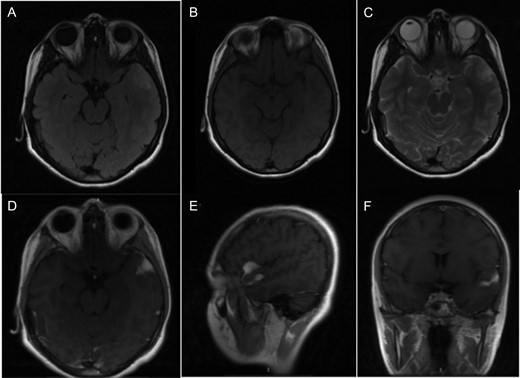

A 14-year-old female with no relevant medical history was referred to the emergency department for the presence of one episode of generalized tonic–clonic seizure lasting ~2 min, with 30 min of postictal state. At the time of the evaluation, she was asymptomatic. The physical examination showed a Glasgow coma scale of 15 points, pupils 3 mm diameter, facial symmetry, muscular strength 5/5 in the four limbs, the rest was normal. A simple computerized tomography and magnetic resonance imaging of the brain were requested, which showed a neoplastic lesion with an exophytic component at the level of the Sylvian fissure (Fig. 1).

(A) T2 flair sequence showing a slightly hyperintense lesion. (B) Lesion behaves isointense to brain parenchyma in T1 sequence. (C) Hyperintense in T2 sequence. (D–F) Axial, sagittal and coronal images, respectively, with contrast enhancement of the tumor.